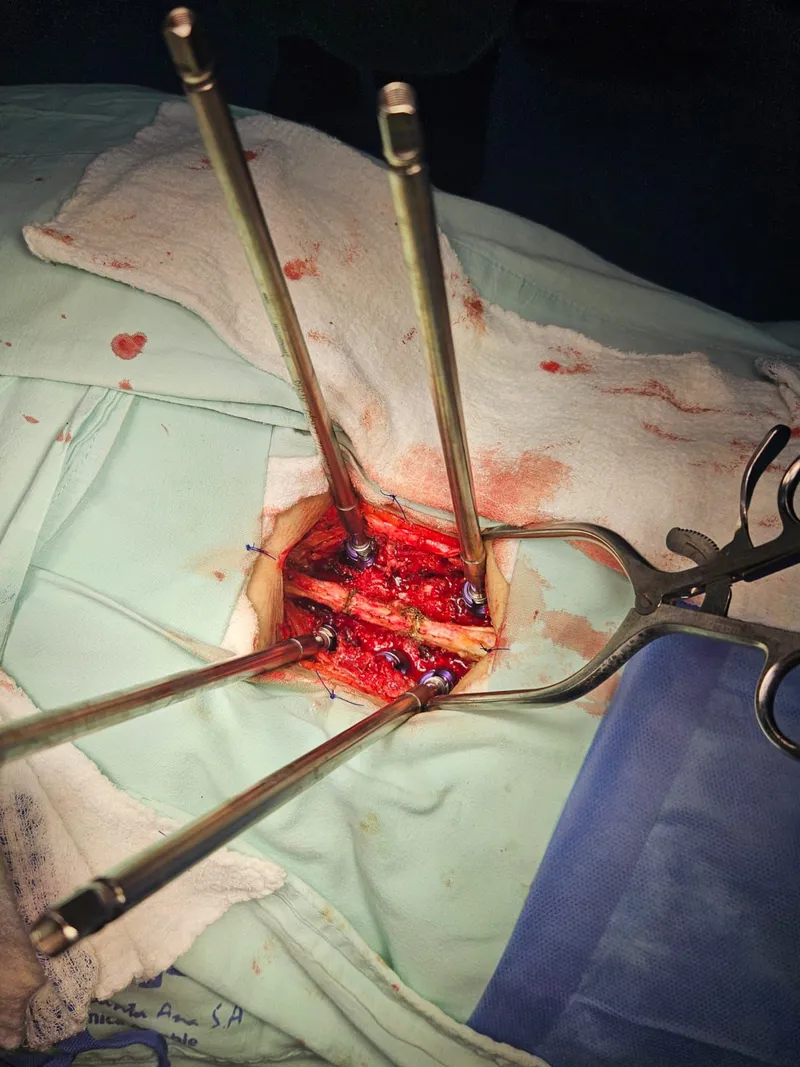

- Inserción de tornillos pediculares cementados: se colocaron los tornillos a través de los pedículos vertebrales, cada uno con inyección previa de cemento óseo para maximizar la fijación en el hueso osteoporótico.

- Conexión con barras: los tornillos se conectaron con barras metálicas que inmovilizan el segmento y permiten la fusión ósea.

- Verificación con fluoroscopio: durante toda la cirugía se utilizó fluoroscopia (rayos X en tiempo real) para confirmar la posición exacta de cada tornillo.